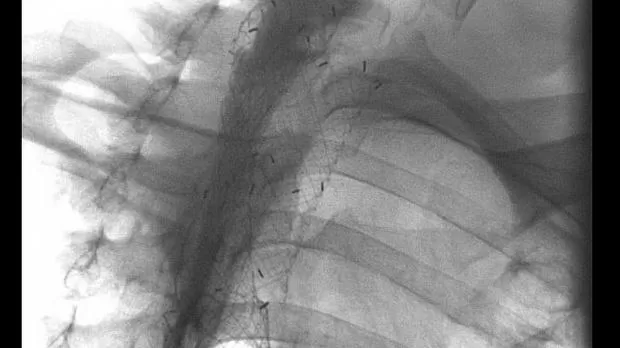

В двух случаях при наличии дисфагии и диспноэ первым этапом выполнена установка саморасправляющегося металлического стента в трахею под эндоскопическим контролем. Длина стента 6 см, диаметр 20 и 22 мм. Через 2 и 4 дня после этого была выполнена установка металлического саморасправляющегося стента в пищевод. Длина стентов по 12 см и диаметр 18 мм. Из-за «высокой» локализации верхнего края сужения по отношению к глоточно-пищеводному переходу применены асимметричный и шеечный стенты. Установка стентов осуществлена под рентгенологическим контролем. Осложнений в процессе выполнения вмешательств не было. Проходимость пищевода была восстановлена.

Длина участка сужения в 5 случаях составила 3,5 см и у одного пациента 4 см. При сдавлении трахеи (4 пациента) устанавливались саморасправляющиеся полностью покрытые металлические стенты длиной 6 см и диаметром 20 (1) и 22 мм (3 пациента). При прорастании опухоли в просвет трахеи с сужением ее просвета в одном случае выполнено стентирование металлическим саморасправляющимся стентом (длина 6 см, диаметр 20 мм), в другом после предварительного бужирования суженного участка трахеи тубусами ригидного бронхоскопа Friedel был установлен силиконовый стент 10х16 мм типа Dumon, длиной 6 см. Осложнений в процессе проведения вмешательства не было.

При проведении имплантации стента в трахею предпочтение отдавалось вмешательствам на самостоятельном дыхании под эндоскопическим контролем (7 пациентов) с применением внутривенной и местной анестезии. Такой способ установки стента сложнее технически, но проще для пациента, особенно при сдавлении трахеи извне, когда существует риск возникновения асфиксии при использовании тотальной внутривенной анестезии с введением миорелаксантов. Во всех случаях при использовании этого способа у половины пациентов была II степень сужения (от 1/2 до 2/3 от ее нормального диаметра), у второй половину сужение носило критический характер (III степень – более 2/3 от ее нормального диаметра). Несмотря на это, фибробронхоскоп с умеренным сопротивлением или свободно проводился ниже участка сужения. После этого по металлической струне-проводнику в зону сужения заводился стент в доставочном устройстве с его постепенным раскрытием. Во всех 7 наблюдениях стенты были установлены в правильную позицию. Практически сразу же после установки (через 5-10 минут) происходило уменьшение одышки и восстановление дыхания. Полное раскрытие стента происходило в течение 10-12 часов, что контролировалось томографией трахеи и фибротрахеобронхоскопией.